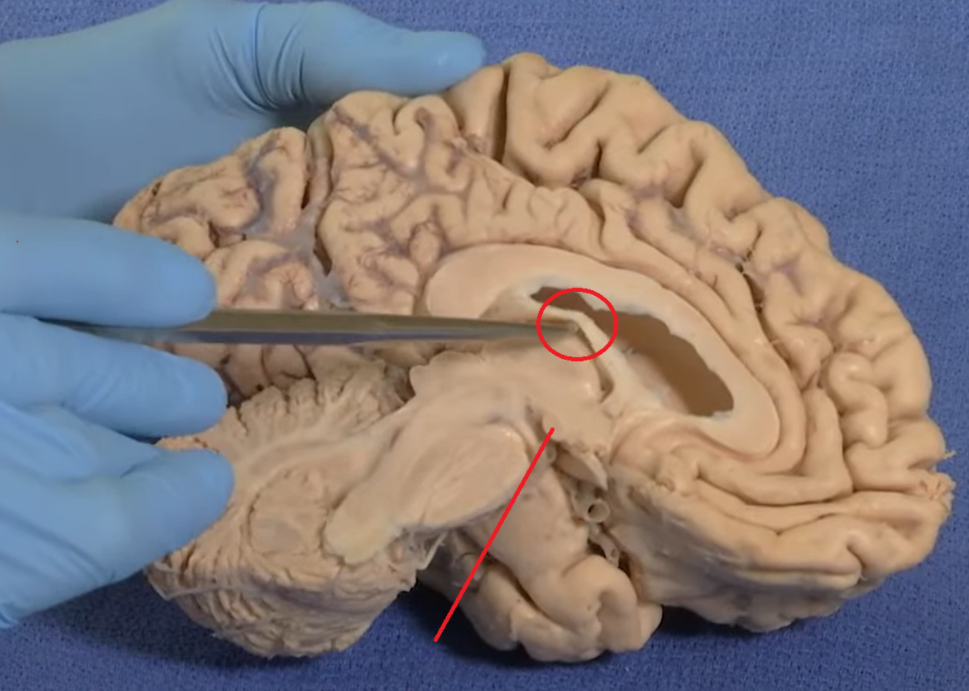

Overlaying the green cingulate and parahippocampal gyri with the purple hippocampus highlights the limbic lobe. Yellow = fornix. Brownish pink = hypothalamus

The purple hippocampus is visualized tracing the ventricular system (turquoise).